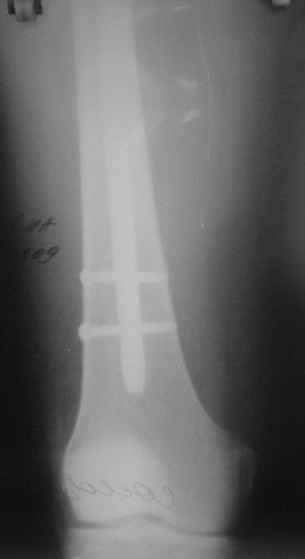

На операции я оставил осколок в области приводящих мышц бедра (ни пальпаторно, ни спицей сдвинуть не смог, "заклинило" насмерть). Фото спустя 2 месяца после операции (PFN).

Только сейчас пациент стал более или менее активным. Сразу после операции жалобы на сильные боли при отведении и приведении бедра в области отломка. Сейчас отломок пальпируется и пациент испытывает дискомфорт, хотя амплитуда движений объективно прогрессирует.

Теперь думаю, надо все-таки было через минидоступ или резецировать, либо репонировать. Обычно при таких операциях уже на 2-й день пациенты на костыли и по отделению, а у этого задержка длительная получилась. Только спустя 2 недели кое-как на костыли взобрался. Ни отека, никакой неврологии, только эти боли в области осколка.